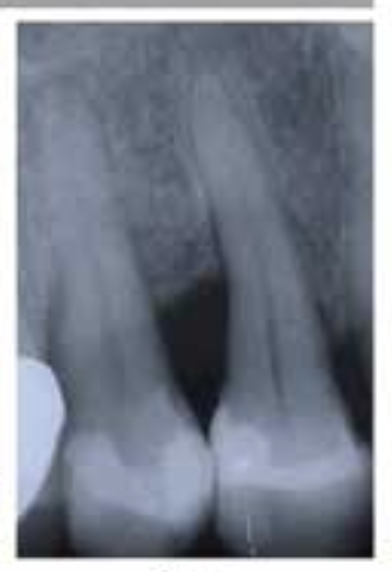

🦷 X-ray 비교

BEFORE

AFTERX-ray 상으로 명확하게 보이는 뼈 재생 효과

1Patient 1: 8년 장기 추적 케이스

치료 시작 전 상태

뼈 재생 진행 확인

재생된 뼈의 장기 유지 확인

✨ 핵심 포인트: Emdogain 치료 후 3년에 걸쳐 점진적으로 재생된 치조골이 8년이 지난 후에도 안정적으로 유지되고 있음을 확인할 수 있습니다. 이는 Emdogain의 장기적인 효과와 안정성을 보여주는 중요한 임상 증거입니다.